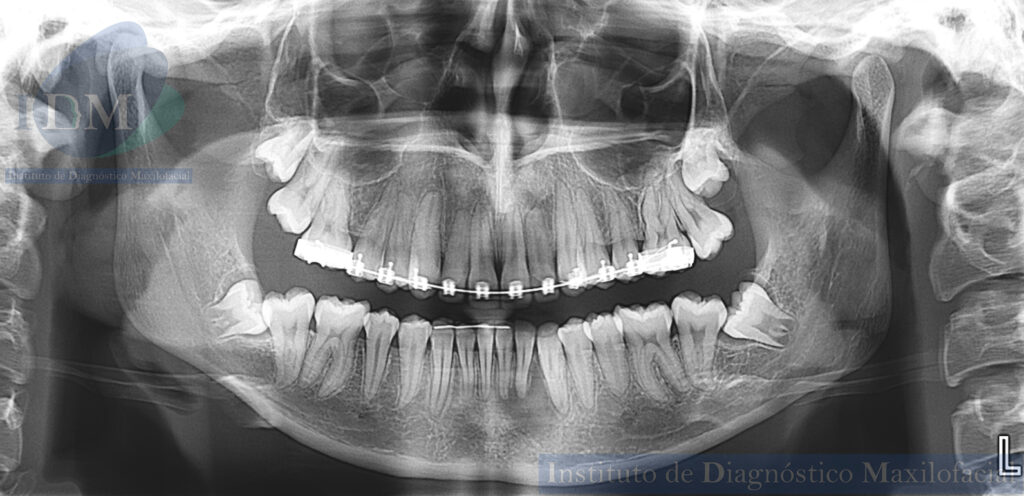

En la radiografía panorámica (Figura 1), se aprecia proceso osteolítico periapical en pieza 32.

Radiografia Panorámica